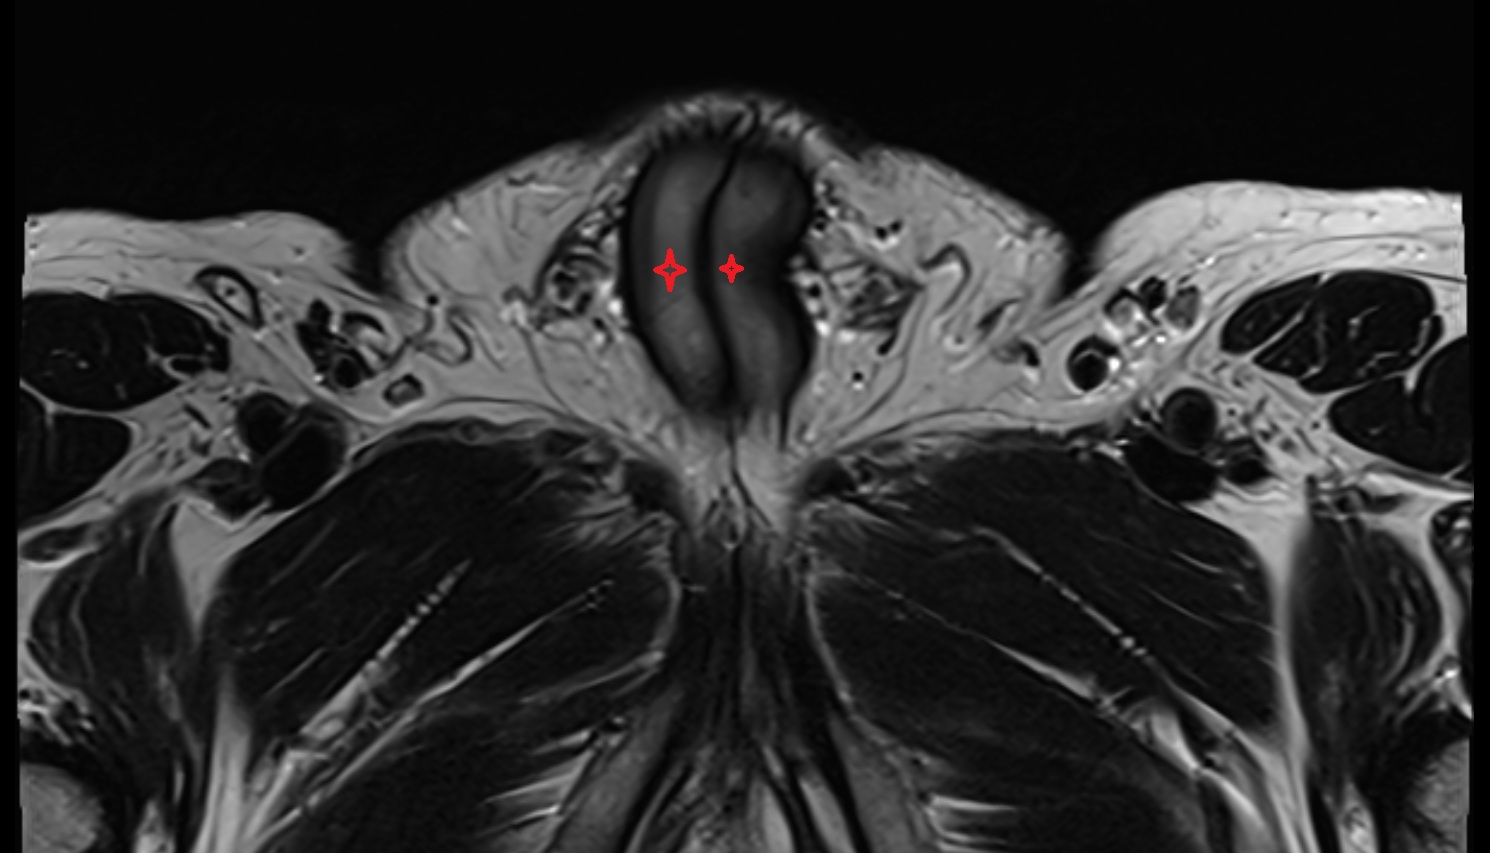

- Peripheral zone of prostate

- Anterior Fibromuscular Stroma of prostate

- Central zone of prostate

- Transitional zone of prostate